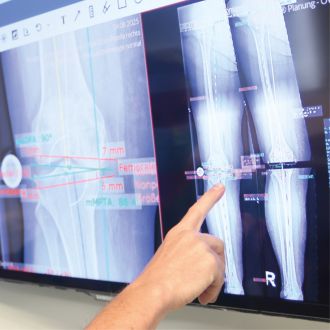

Knieendoprothetik

Dank roboterassistierter Kniechirurgie lassen sich Implantate besonders präzise einsetzen und die Funktion des Gelenks nachhaltig verbessern.